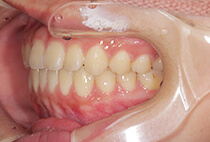

治療前

治療後

八重歯の見た目が気になってご来院されましたが、実は顎の痛みや開口障害など、顎関節症の症状もありました。

そのため、かみ合わせと顎関節症の治療を同時に行ったにもかかわらず、2年間で治療が終了。

かみ合わせが整い咬筋の過緊張も改善しました。咬筋の肥大も治ってフェイスラインがすっきりしました。

最終的には美しい歯並びと、安定した痛みのないかみ合わせが実現しました。

しっかり前歯を下げるために、インプラントアンカーを使用してコントロールしました。

かみ合わせが整うと咬筋の過緊張が改善。

過緊張による筋肉肥大も改善しフェイスラインもすっきりしました。